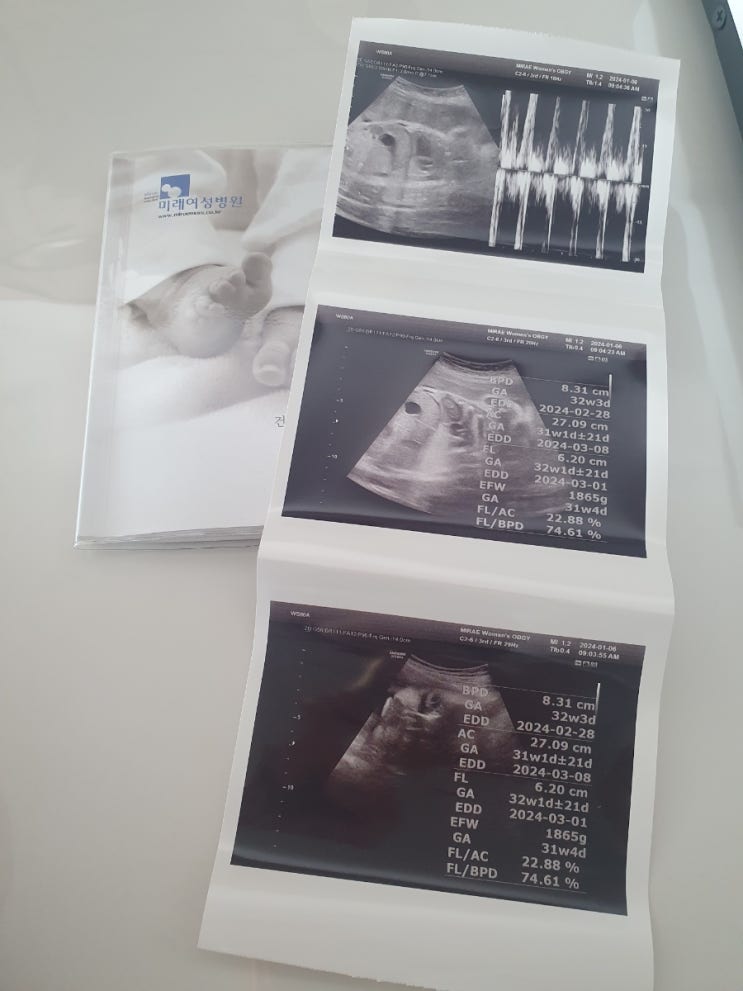

33주 1일째.

-2024년 1월 6일 토요일- 24년 되고 처음으로 튼튼이 보러가는 날♡ 4주에 한번씩 가다가 이제는 2주에 한...